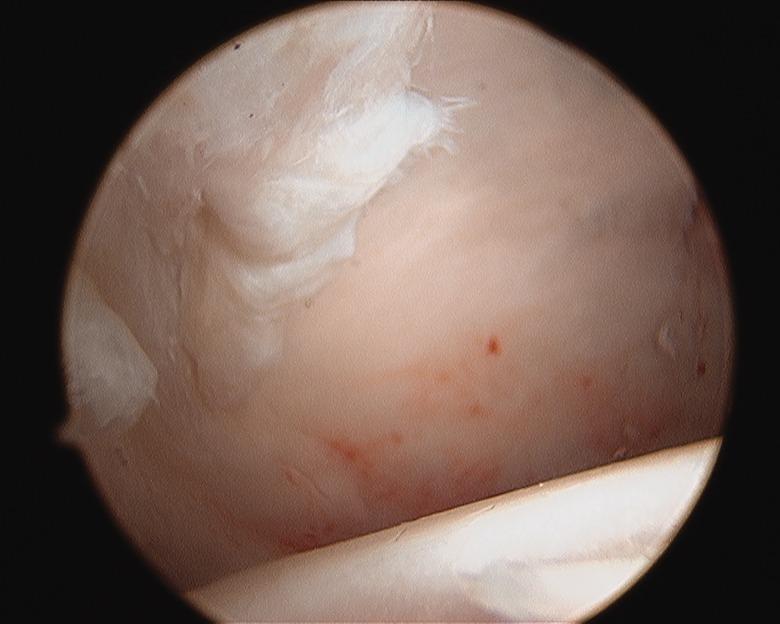

Arthroscopy of the pediatric hip began in 1977 with a publication by Gross. Interest was relatively slow to develop in the 1980s and 1990s. Coupled with the success of hip arthroscopy in the adult, interest heightened in applying the procedure to a variety of pediatric hip disorders, given that the alternative was an open surgical hip dislocation. The success of this initial group of pediatric hip arthroscopist's has further expanded the application of hip arthroscopy as the primary or adjunct procedure for the management of intra-articular problems of the pediatric hip.

小儿髋关节镜检查始于1977年格罗斯发表的一篇文章。在20世纪80年代和90年代,其发展相对缓慢。鉴于成人髋关节镜手术的成功,加上替代方案是开放性髋关节脱位手术,人们对将该手术应用于各种小儿髋关节疾病的兴趣日益浓厚。首批小儿髋关节镜医生取得的成功进一步扩大了髋关节镜检查作为治疗小儿髋关节关节内问题的主要或辅助手术的应用范围。